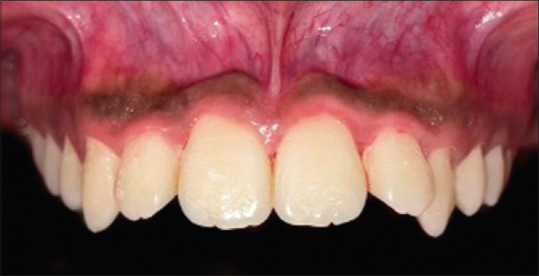

Abstract Image